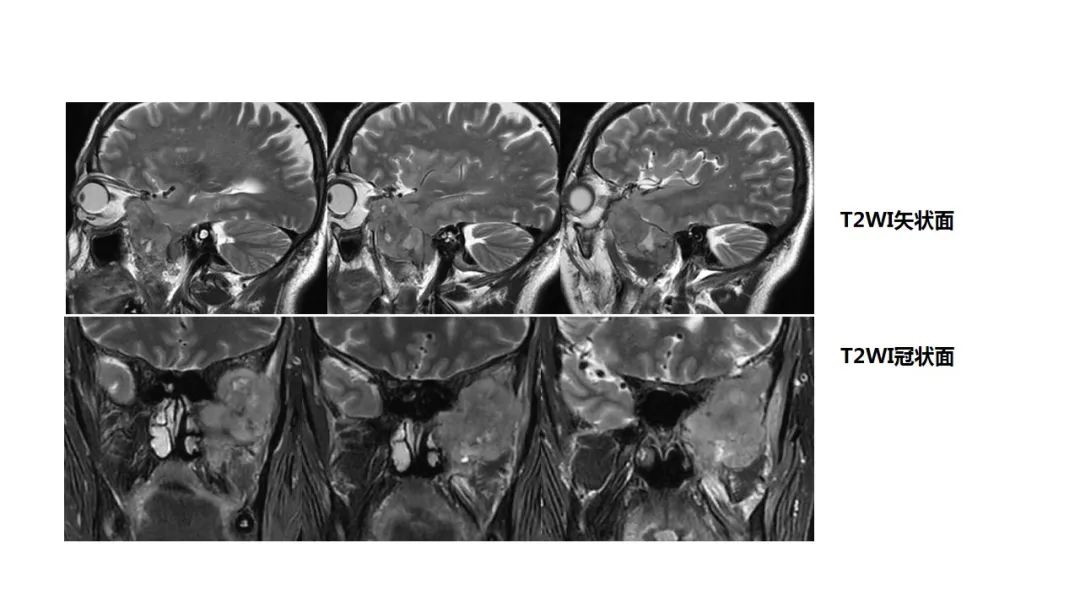

【病例】咬肌间隙肌纤维母细胞肉瘤1例MR诊断与鉴别-1

【病例】咬肌间隙肌纤维母细胞肉瘤1例MR诊断与鉴别-2